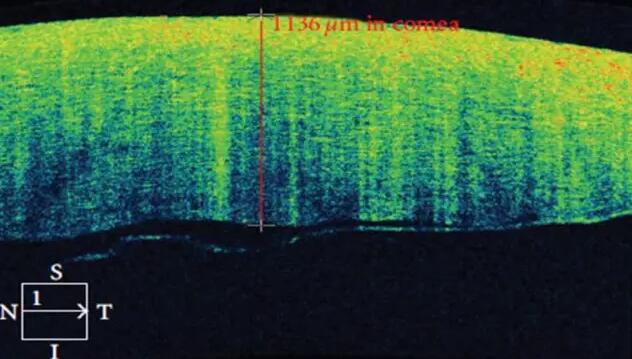

1、角膜分层观察 OCT 轴向分辨率高达5μm,远高于UBM(20--60μm),可识别出泪膜、上皮层、前弹力层、基质层、后弹力层/内皮层

2、角膜厚度评估,角膜水肿、瘢痕、混浊、溃疡、异物、炎症、胬肉等断层观察

3、角膜屈光手术后角膜瓣观察、角膜厚度评估等